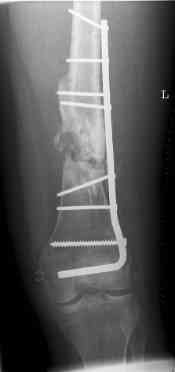

Nov 07

nov 07: persistant non-union distal femur; other fractures healed uneventfully.

All with gradual/partial weightbearing etc. Currently 50-100% weight bearing, no pain.

Soft tissues are intact. No smoking or diabetes.CRP <2

What would you do?